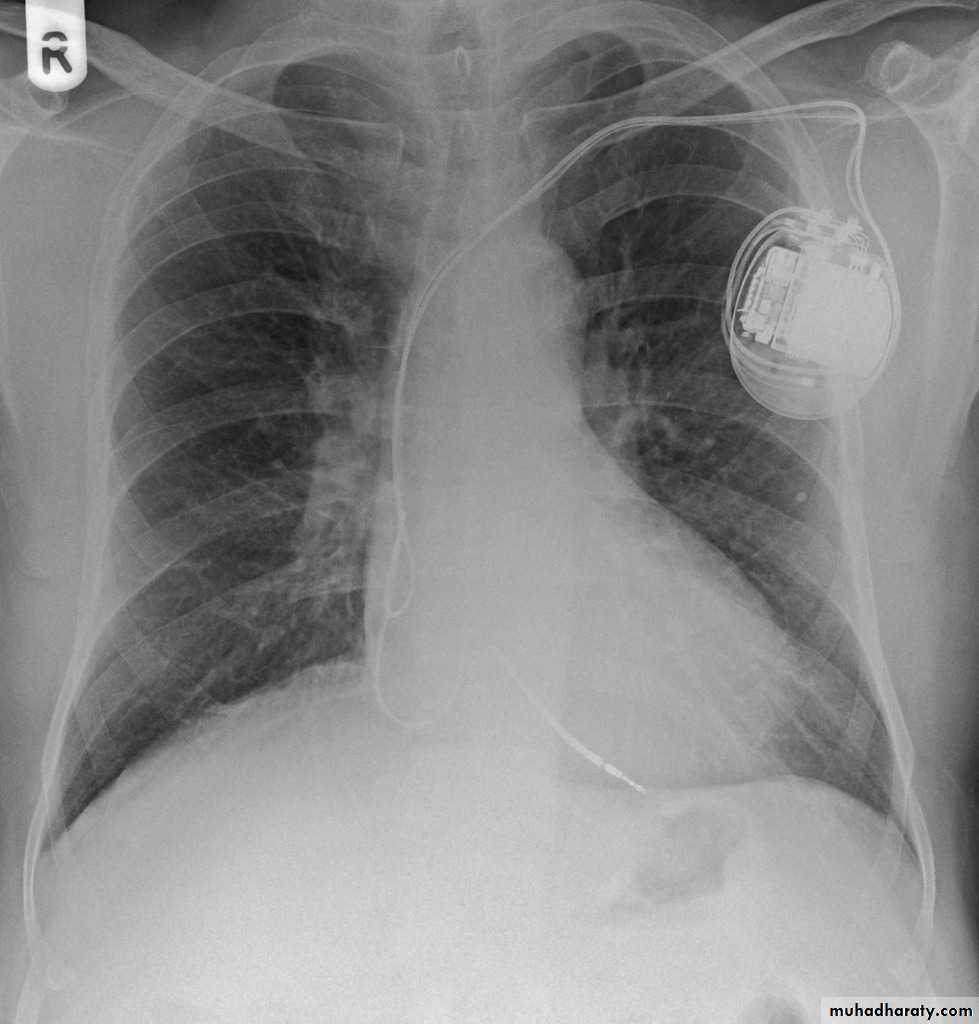

• Check up chest x-ray